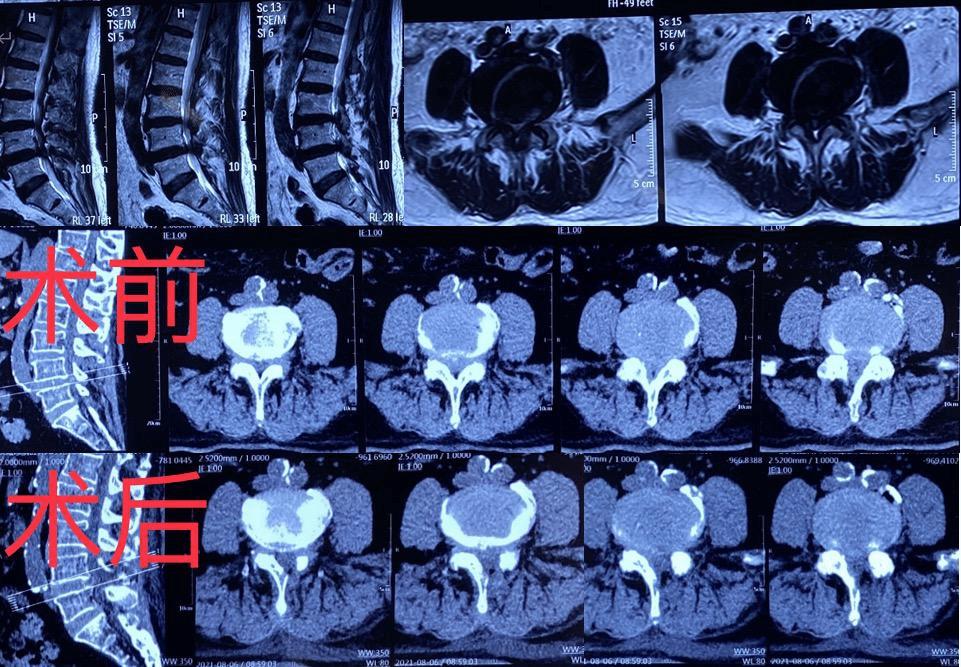

周先生在家人陪伴下,到ac米兰官网中文网站一院群力院区骨科就诊,王岩松经过影像学等相关检查确诊为“腰椎间盘突出症、腰椎管狭窄症”。由于周先生的超高龄且合并高血压、心脏病、脑梗、呼吸系统等基础疾病,手术与全身麻醉风险极高,王岩松团队经过心内科、呼吸内科、神经内科、麻醉科等多学科会诊讨论,完善相关术前检查后,王岩松教授、王义文主治医师在局麻监护下成功为其进行经皮椎间孔镜微创手术,手术共耗时40分钟,出血5ml,仅需缝合1针,术后下肢疼痛、麻木等症状明显缓解,症状恢复良好,术后2天顺利出院。